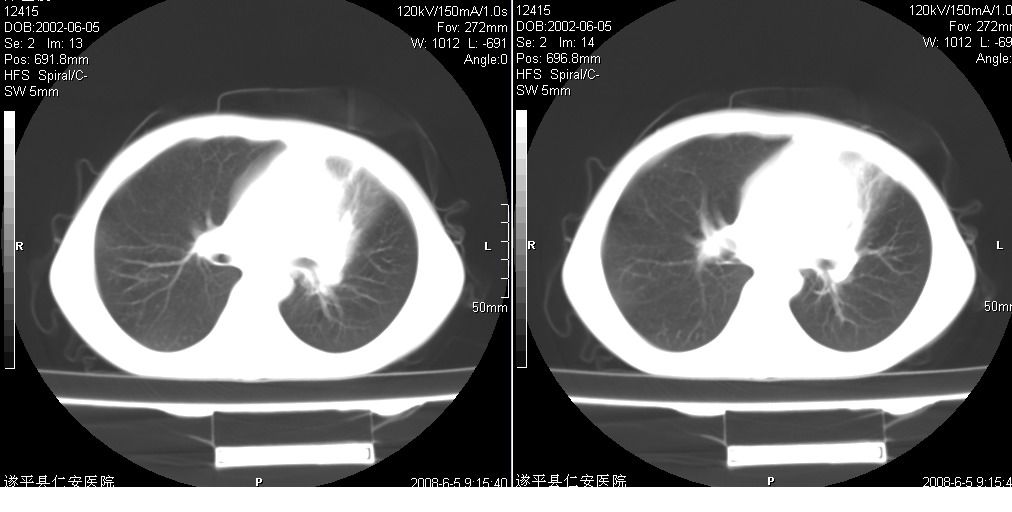

以下是引用xxhwh在2008-6-10 18:40:00的发言:[br]男,6岁,无规则发热一月余,体温在37.8——39度之间。一月前拍胸片示左上肺密度增高影,进行抗炎治疗8天,复查胸片未明显吸收。又改变抗菌素继续治疗半月,照胸片示病灶吸收不明显,行ct检查[br]征象:左上肺前段呈密实影,内可见支气管气像,远侧见絮状模糊影,中上纵隔左移。[br]意见:左上肺前段膨胀不全及感染,考虑为支气管异物或支气管内膜结核所致,[br]建议追问有无异物吸入史,行痰检及ppd检查